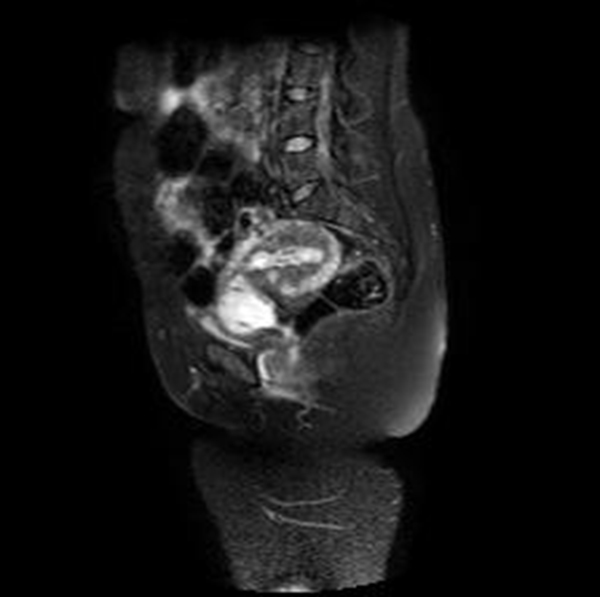

Se realizó una RNM (Philips 1.5 Tesla) que permitió confirmar el diagnóstico de EEC (figuras 5 a 8).

Jung y cols. (28) encontraron como hallazgos en RMN de EEC una masa mal definida con señales muy heterogéneas en T2, hiperintensidades internas e irregulares en T1, con un anillo circunferencial o parcial de baja intensidad de señal, con realce periférico irregular del componente sólido papilar, acompañado de vacíos de señal de morfología tubular. Esto va en concordancia con lo referido por Tamai y cols. (27), que describen típicamente el EEC como una masa hemorrágica, heterogénea y con realce intenso de los componentes papilares del tejido.

Una secuencia útil en la identificación del hematoma reciente es el T2*, que podría remplazar el uso del gadolinio en esta indicación particular. La sensibilidad del 95 % y la especificidad del 100 % de esta secuencia mejora significativamente el desempeño de la resonancia en el diagnóstico de EE (29).

El uso de gadolinio intravenoso incrementa la especificidad en el diagnóstico de embarazo tubárico, lo que permite diferenciar el realce normal de la trompa de un hematoma reciente. En este caso, este principio nos ayudó a delimitar la afectación decidual y a descartar la presencia de un hematoma asociado (30). La resonancia con gadolinio también se ha utilizado en el seguimiento del tratamiento conservador del EEC (31).